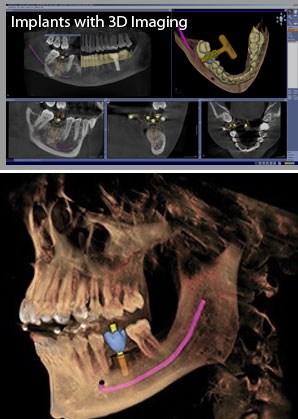

Implants with and without 3D imaging In implant treatment planning, we have come to hold the strong opinion that the standard of care today in implant dentistry is to recommend 3-D imaging for implants for nearly every patient, and because of this it would be poor practice to do implants without using 3-D imaging.

Cone Beam Volumetric Tomography is a diagnostic imaging technology that uses radiation in a manner similar to conventional radiographic imaging, with the difference being that cone beam images are converted into a three-dimensional view that can then be manipulated by sophisticated computer software for a wide variety of applications, including implant, endodontic, orthodontic,periodontic , orthognathic ,TMJ, and diagnostic purposes.